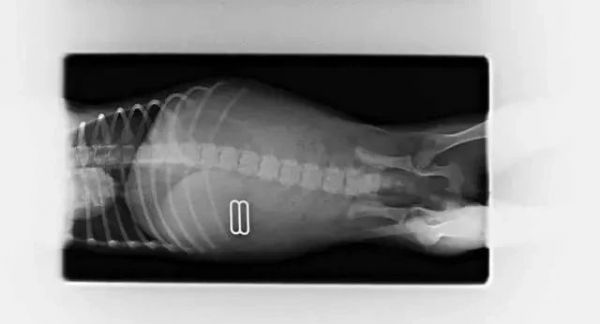

呃嗯......这货干脆吞下了女主人的bra。